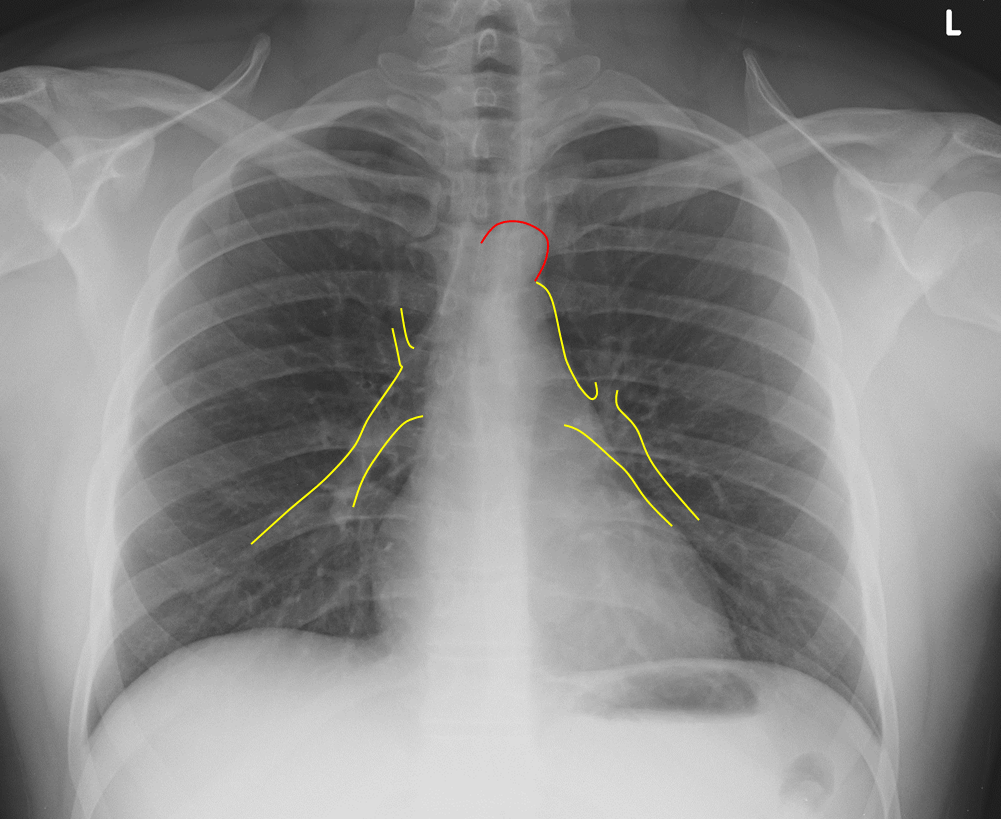

How To Determine Rotation On Chest X Ray . This patient is rotated to their left (right shoulder forwards and left shoulder backwards) the spinous. But before we interpret a chest xray, is is helpful to check the following: This can make structures (like the heart) appear larger/smaller then they really are. If the patient is rotated to their left, then the heart may appear enlarged. If the patient is rotated to their right, then heart size may be underestimated. Assess adequacy of the film. A small amount of patient rotation can lead to misinterpretation. We present a novel method for detecting rotated lungs in chest radiographs for quality control and augmenting automated abnormality detection.